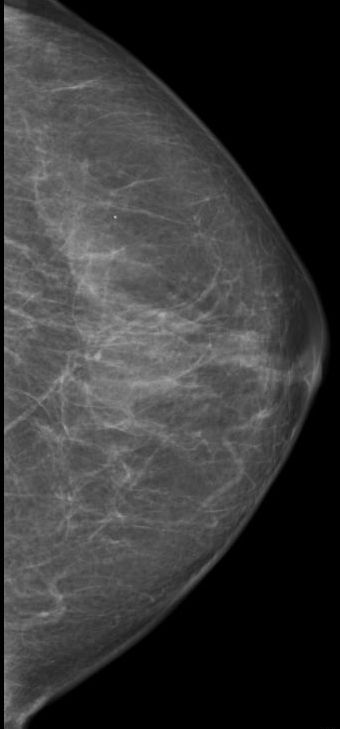

| Mammographie | 76-jährige Patientin mit multiplen Metastasen in Wirbelsäule und Leber. Zunächst kein Tastbefund der Brust. Dann suspekter Tastbefund rechts oben außen paramamillär. Mammographie zunächst o.B. befundet. Stanzbiopsie rechts oben außen: lobuläres Karzinom. | |||||||||